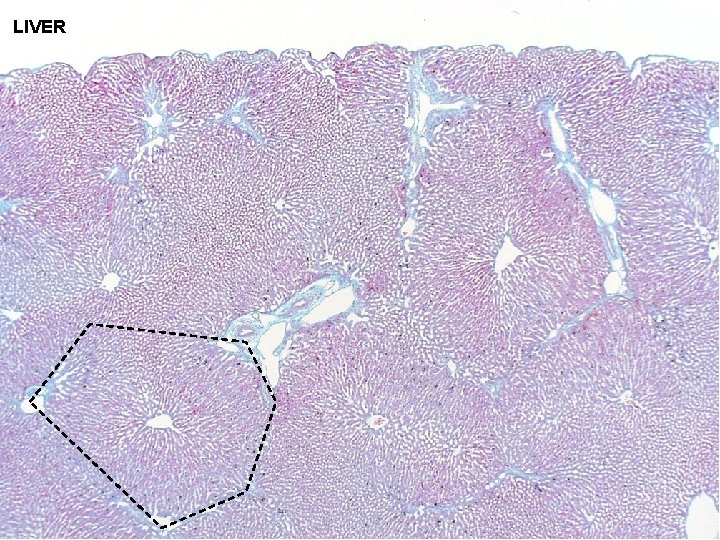

ACCESSORY DIGESTIVE GLANDS - central vein at LIVER center - hexagonal in shape - portal triad at corners - portal triad at center - triangular in shape - central vein at corners CLASSIC LOBULE PORTAL LOBULE - short axis: branches of portal triad between 2 classic - lobules long axis: between 2 central veins LIVER ACINUS

LIVER

ACCESSORY DIGESTIVE GLANDS LIVER